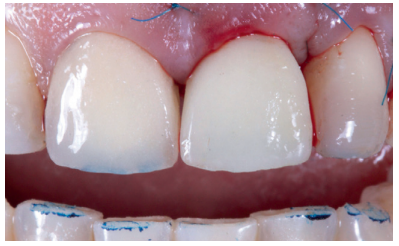

Se presenta el caso clínico de una mujer de 52 años de edad, que acudió a la consulta odontológica debido al descementado de una corona metal-cerámica dentosoportada en el diente 2.1 (ICSI) (Figuras 1-3). La paciente refería una alta preocupación por su estética.

Utilizando el escáner 3Shape®, se realizó un pre-escaneado intraoral, primero con la corona dentosoportada colocada, para obtener la anatomía del incisivo central, y después sin ésta, escaneando así el perfil de emergencia del resto radicular; se informó al laboratorio de la modificación del perfil critico, corrigiendo así la recesión existente respecto al 1.1 (Figuras 5-7). Este escaneado sirvió a su vez para la toma de color del futuro provisional7,8. El archivo STL fue enviado al laboratorio protésico para elaborar la prótesis provisional tipo Maryland, en polimetil-metacrilato (PMMA), con dos apoyos en los bordes incisales de los dientes adyacentes para asegurar su correcto posicionamiento que, según la planificación previa, serviría como diente provisional, así como de guía quirúrgica para la inserción del IOI en la posición protésica idónea, evitando así posibles problemas futuros a nivel protésico o en la integridad de los tejidos blandos y duros de la región vestibular (Figuras 8 y 9).